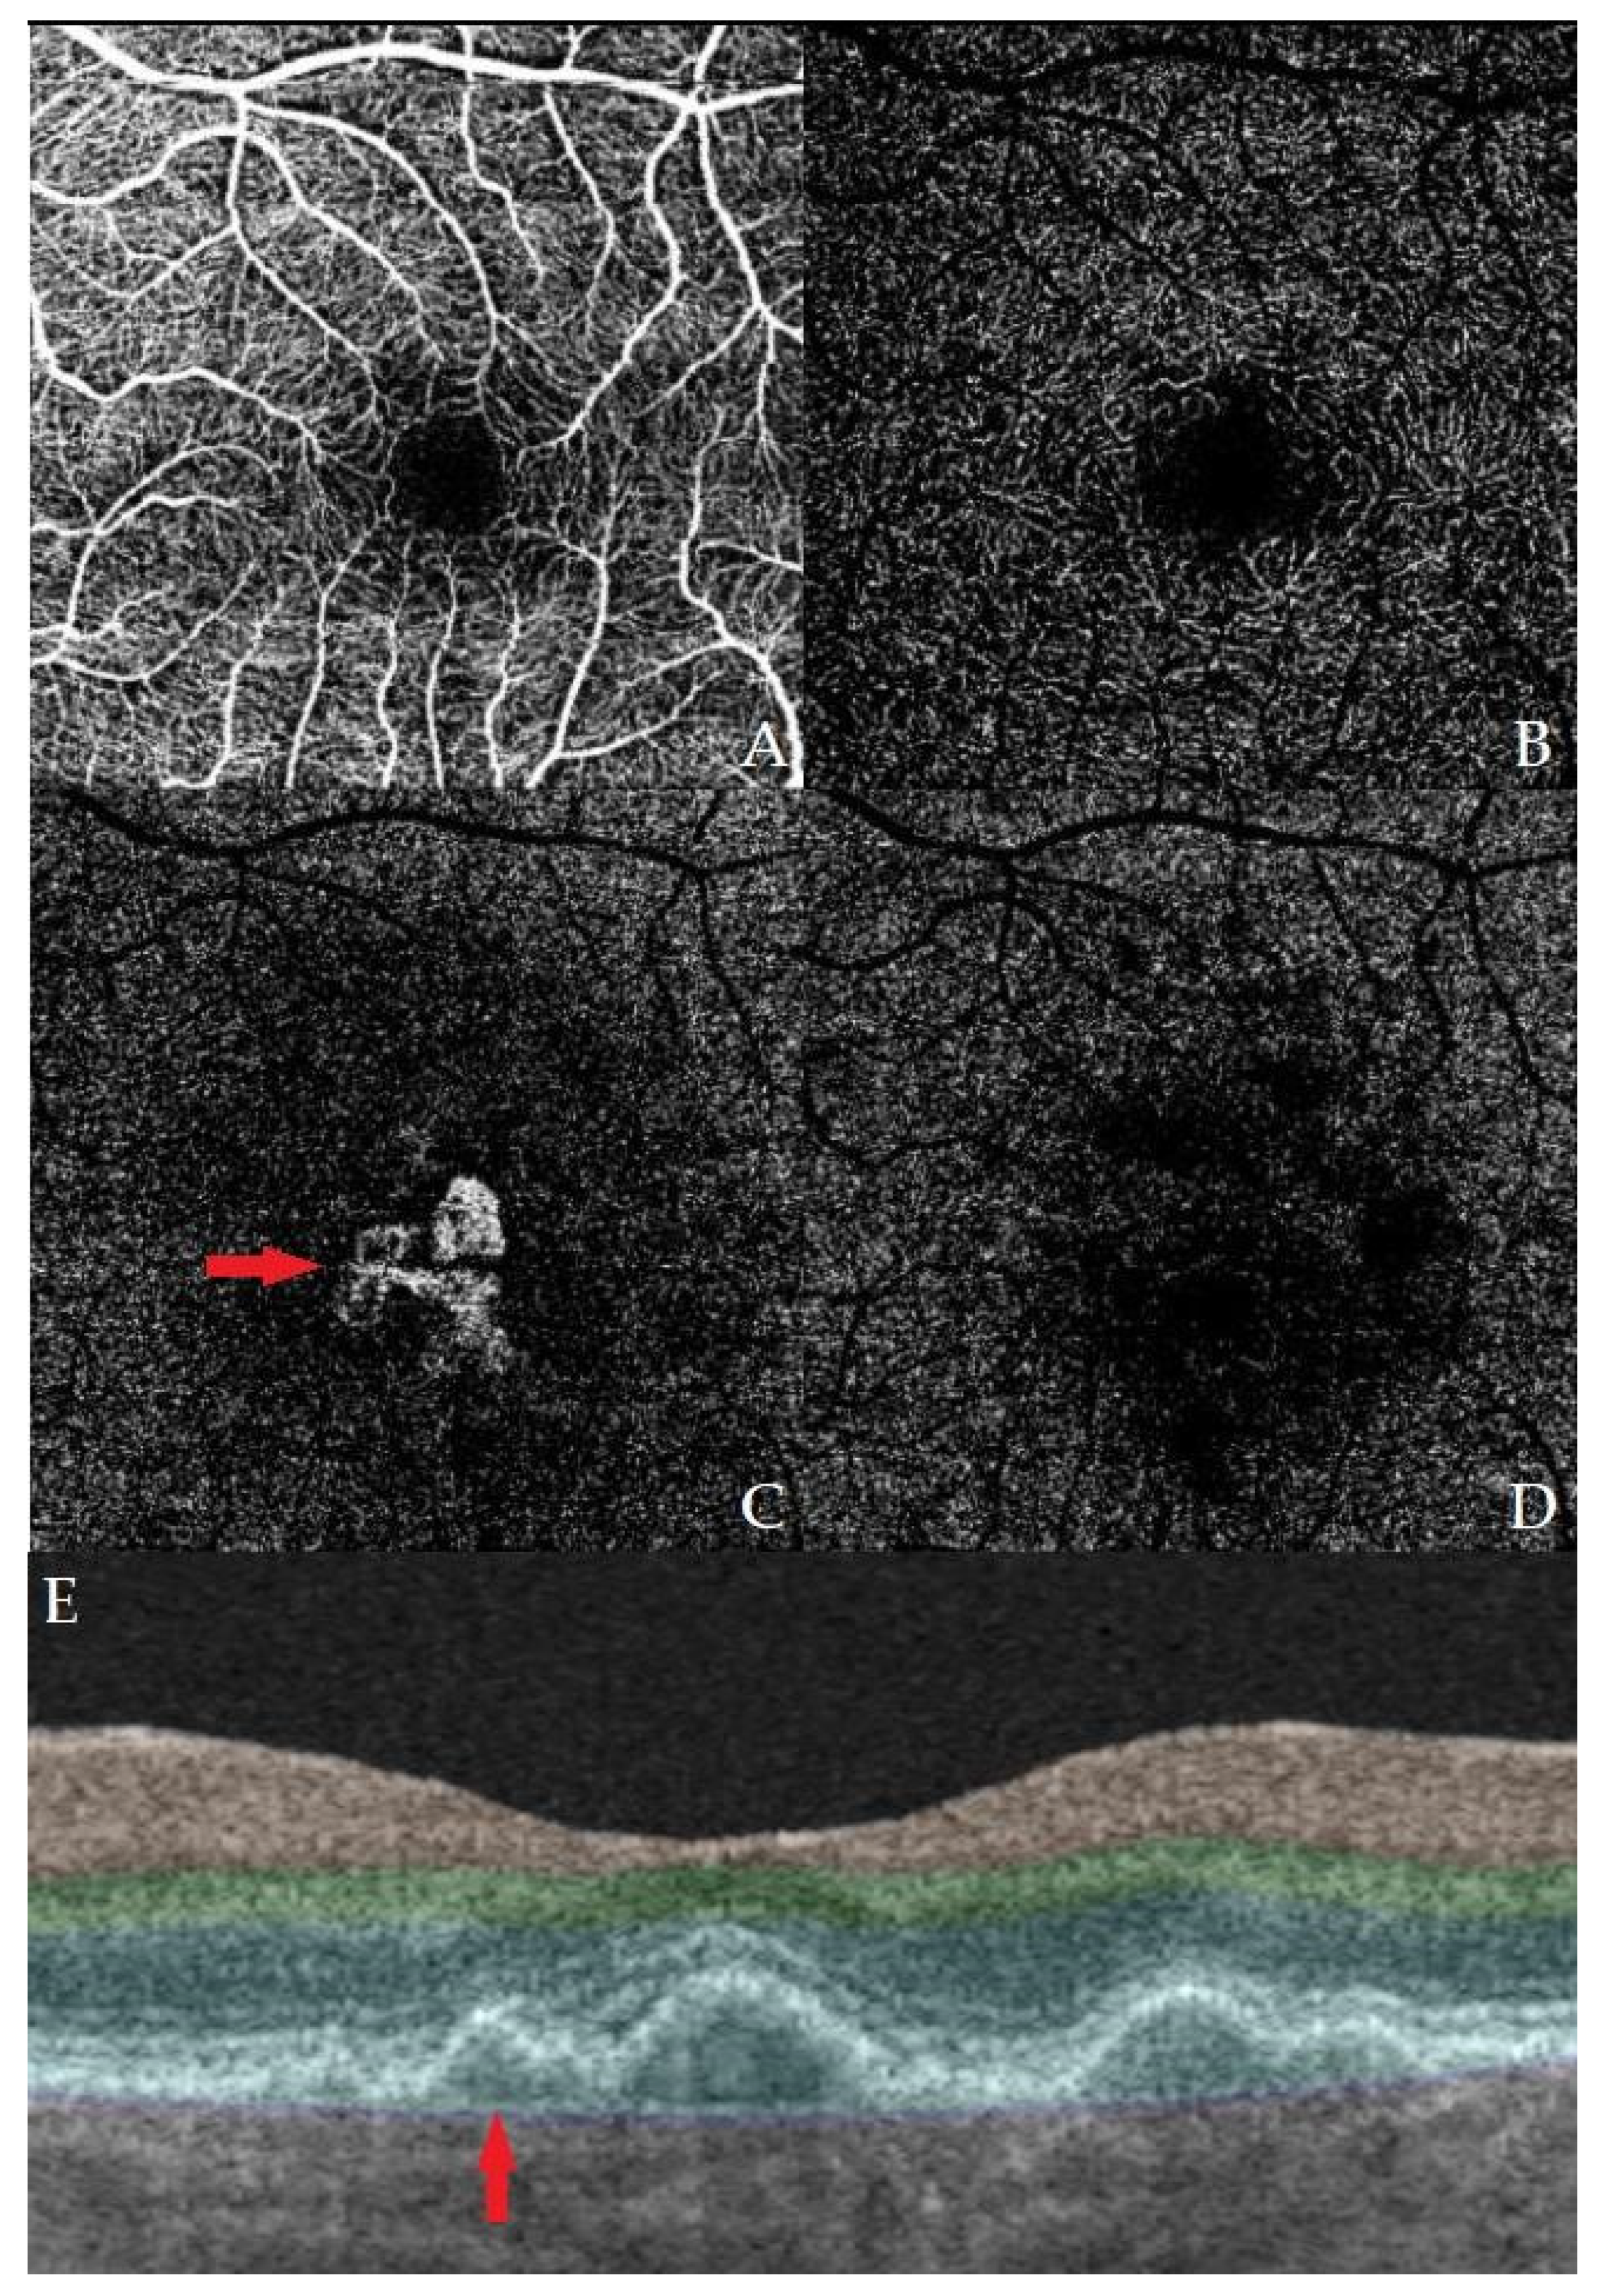

Correlation of the OCT Double-Layer Sign with Type 1 Non-Exudative Neovascularization on OCT-A in Age-Related Macular Degeneration